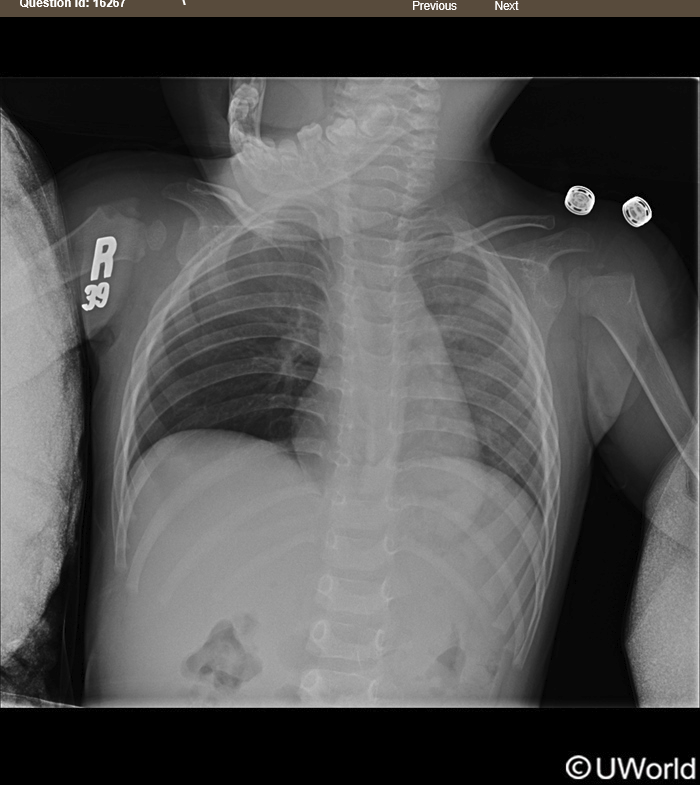

18 month old boy playing with cousin, sudden shortness of breath and wheezing

unilateral lung hyperinflation → foreign body aspiration